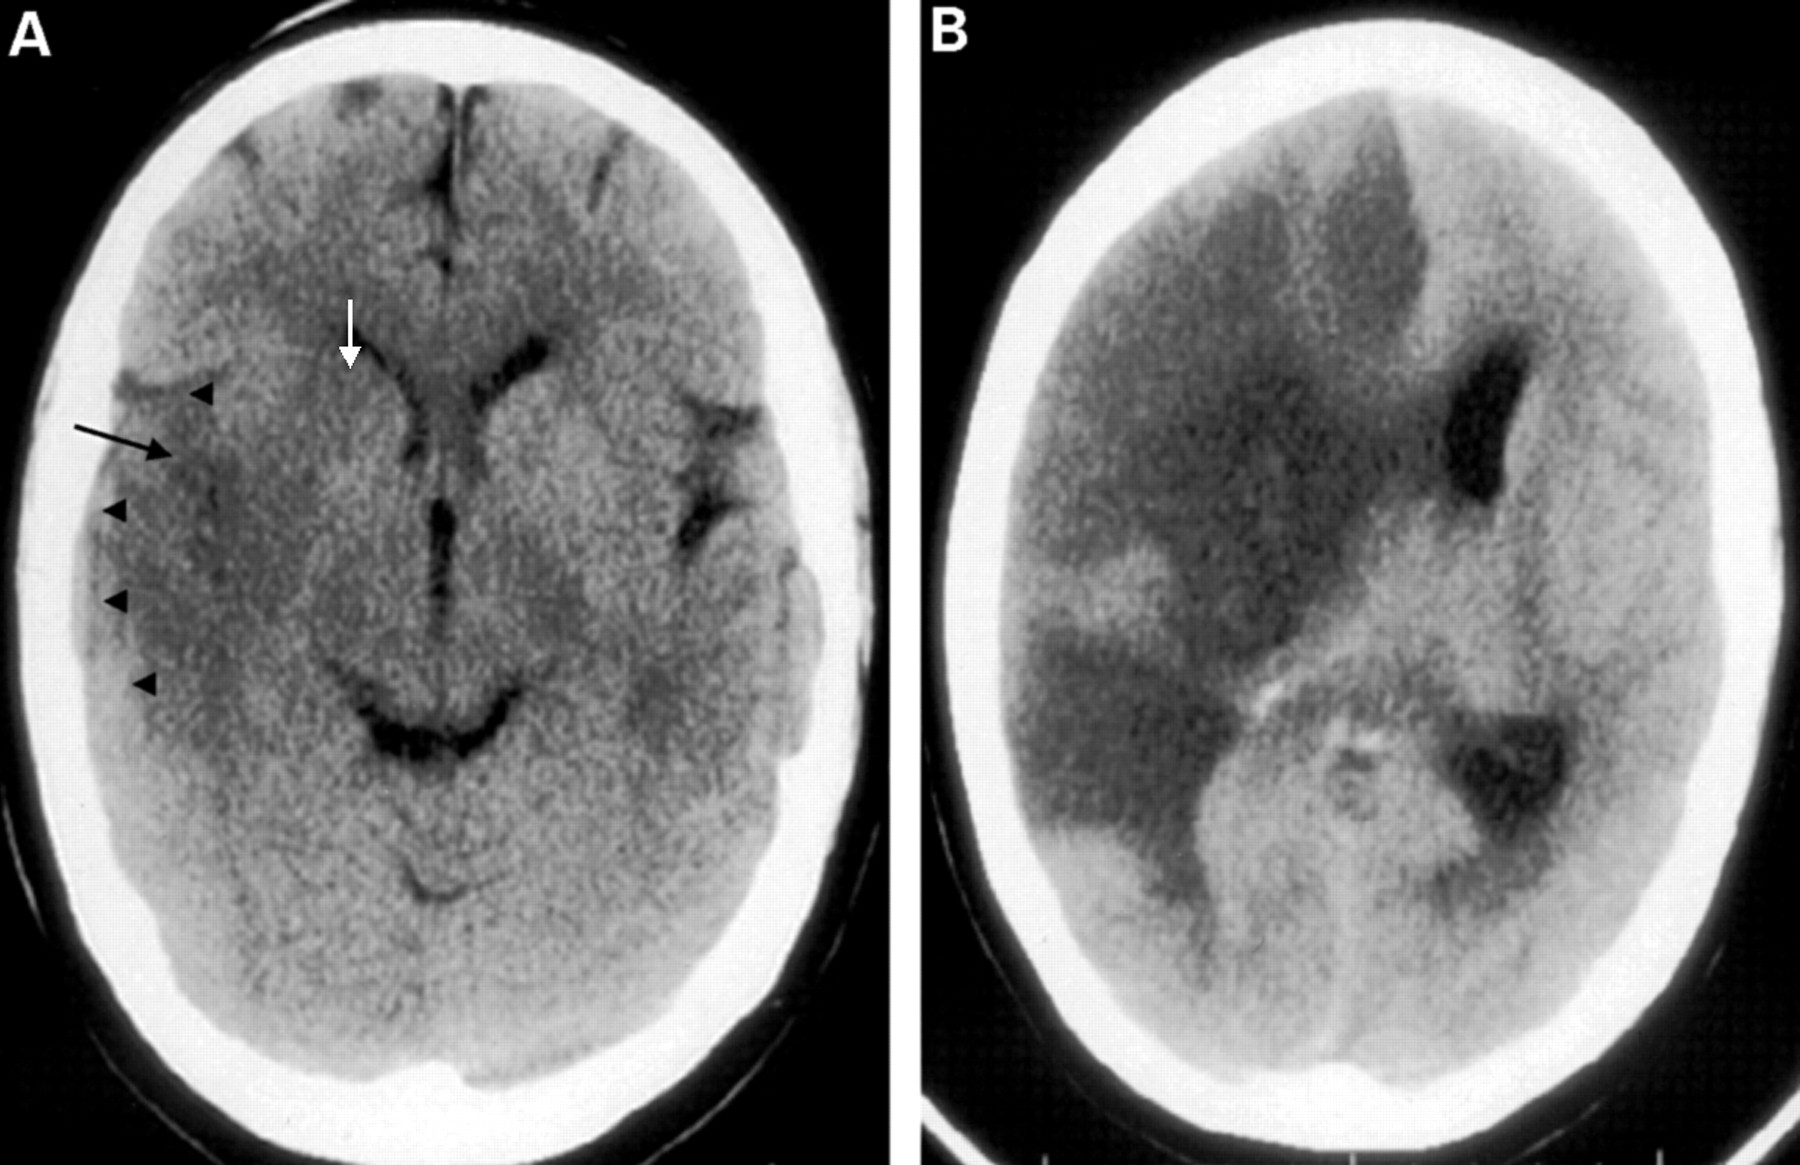

| Subdural haemorrhage | Crescent-shaped hyperdensity along brain surface, crossing suture lines, may track over a large area. Often associated with mass effect and possible midline shift. |

| Epidural haemorrhage | Biconvex (lens-shaped) hyperdensity that typically does not cross suture lines. May cause mass effect and midline shift; commonly related to skull fracture. |

| Intracerebral / intraparenchymal haemorrhage | Hyperdense collection within brain parenchyma with variable mass effect. Appearance depends on location and size; may extend into ventricles. |